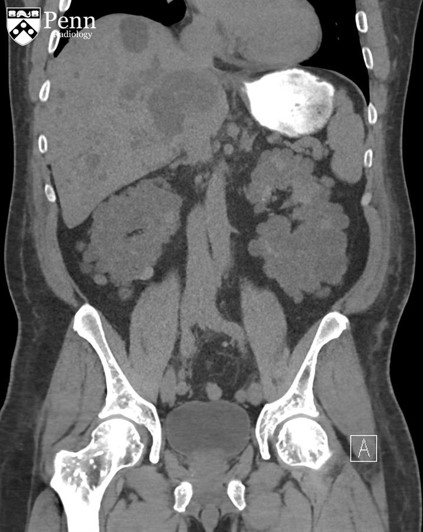

病史 男性,52岁,主诉腹部疼痛伴不明原因菌血症;患者有慢性肾病史。

腹盆CT图像如下

3.根据上面的影像,下面哪个最接近患者肾功能失常的病源学分析?(单选) 常染色体显性遗传多囊肾 常染色体隐性遗传多囊肾 肾脏多囊性发育不良 慢性输尿管膀胱联合障碍 锂肾病